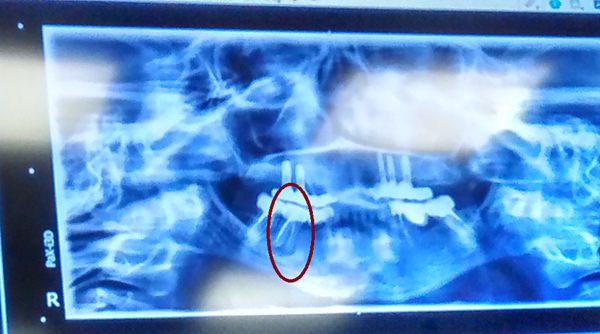

Al poner la radiografía en la pantalla de la tele, nos dijo que viéramos como se veía que la raíz estaba partida, aunque yo veía la raíz exactamente igual que las demás, y cuando se lo comenté, me dijo que no, que se veía perfectamente que esta estaba rota por lo que procedió a la extracción.

Aunque la foto es muy mala, podéis decirme si se ha procedido correctamente, porque sinceramente, empiezo a tener mis dudas.